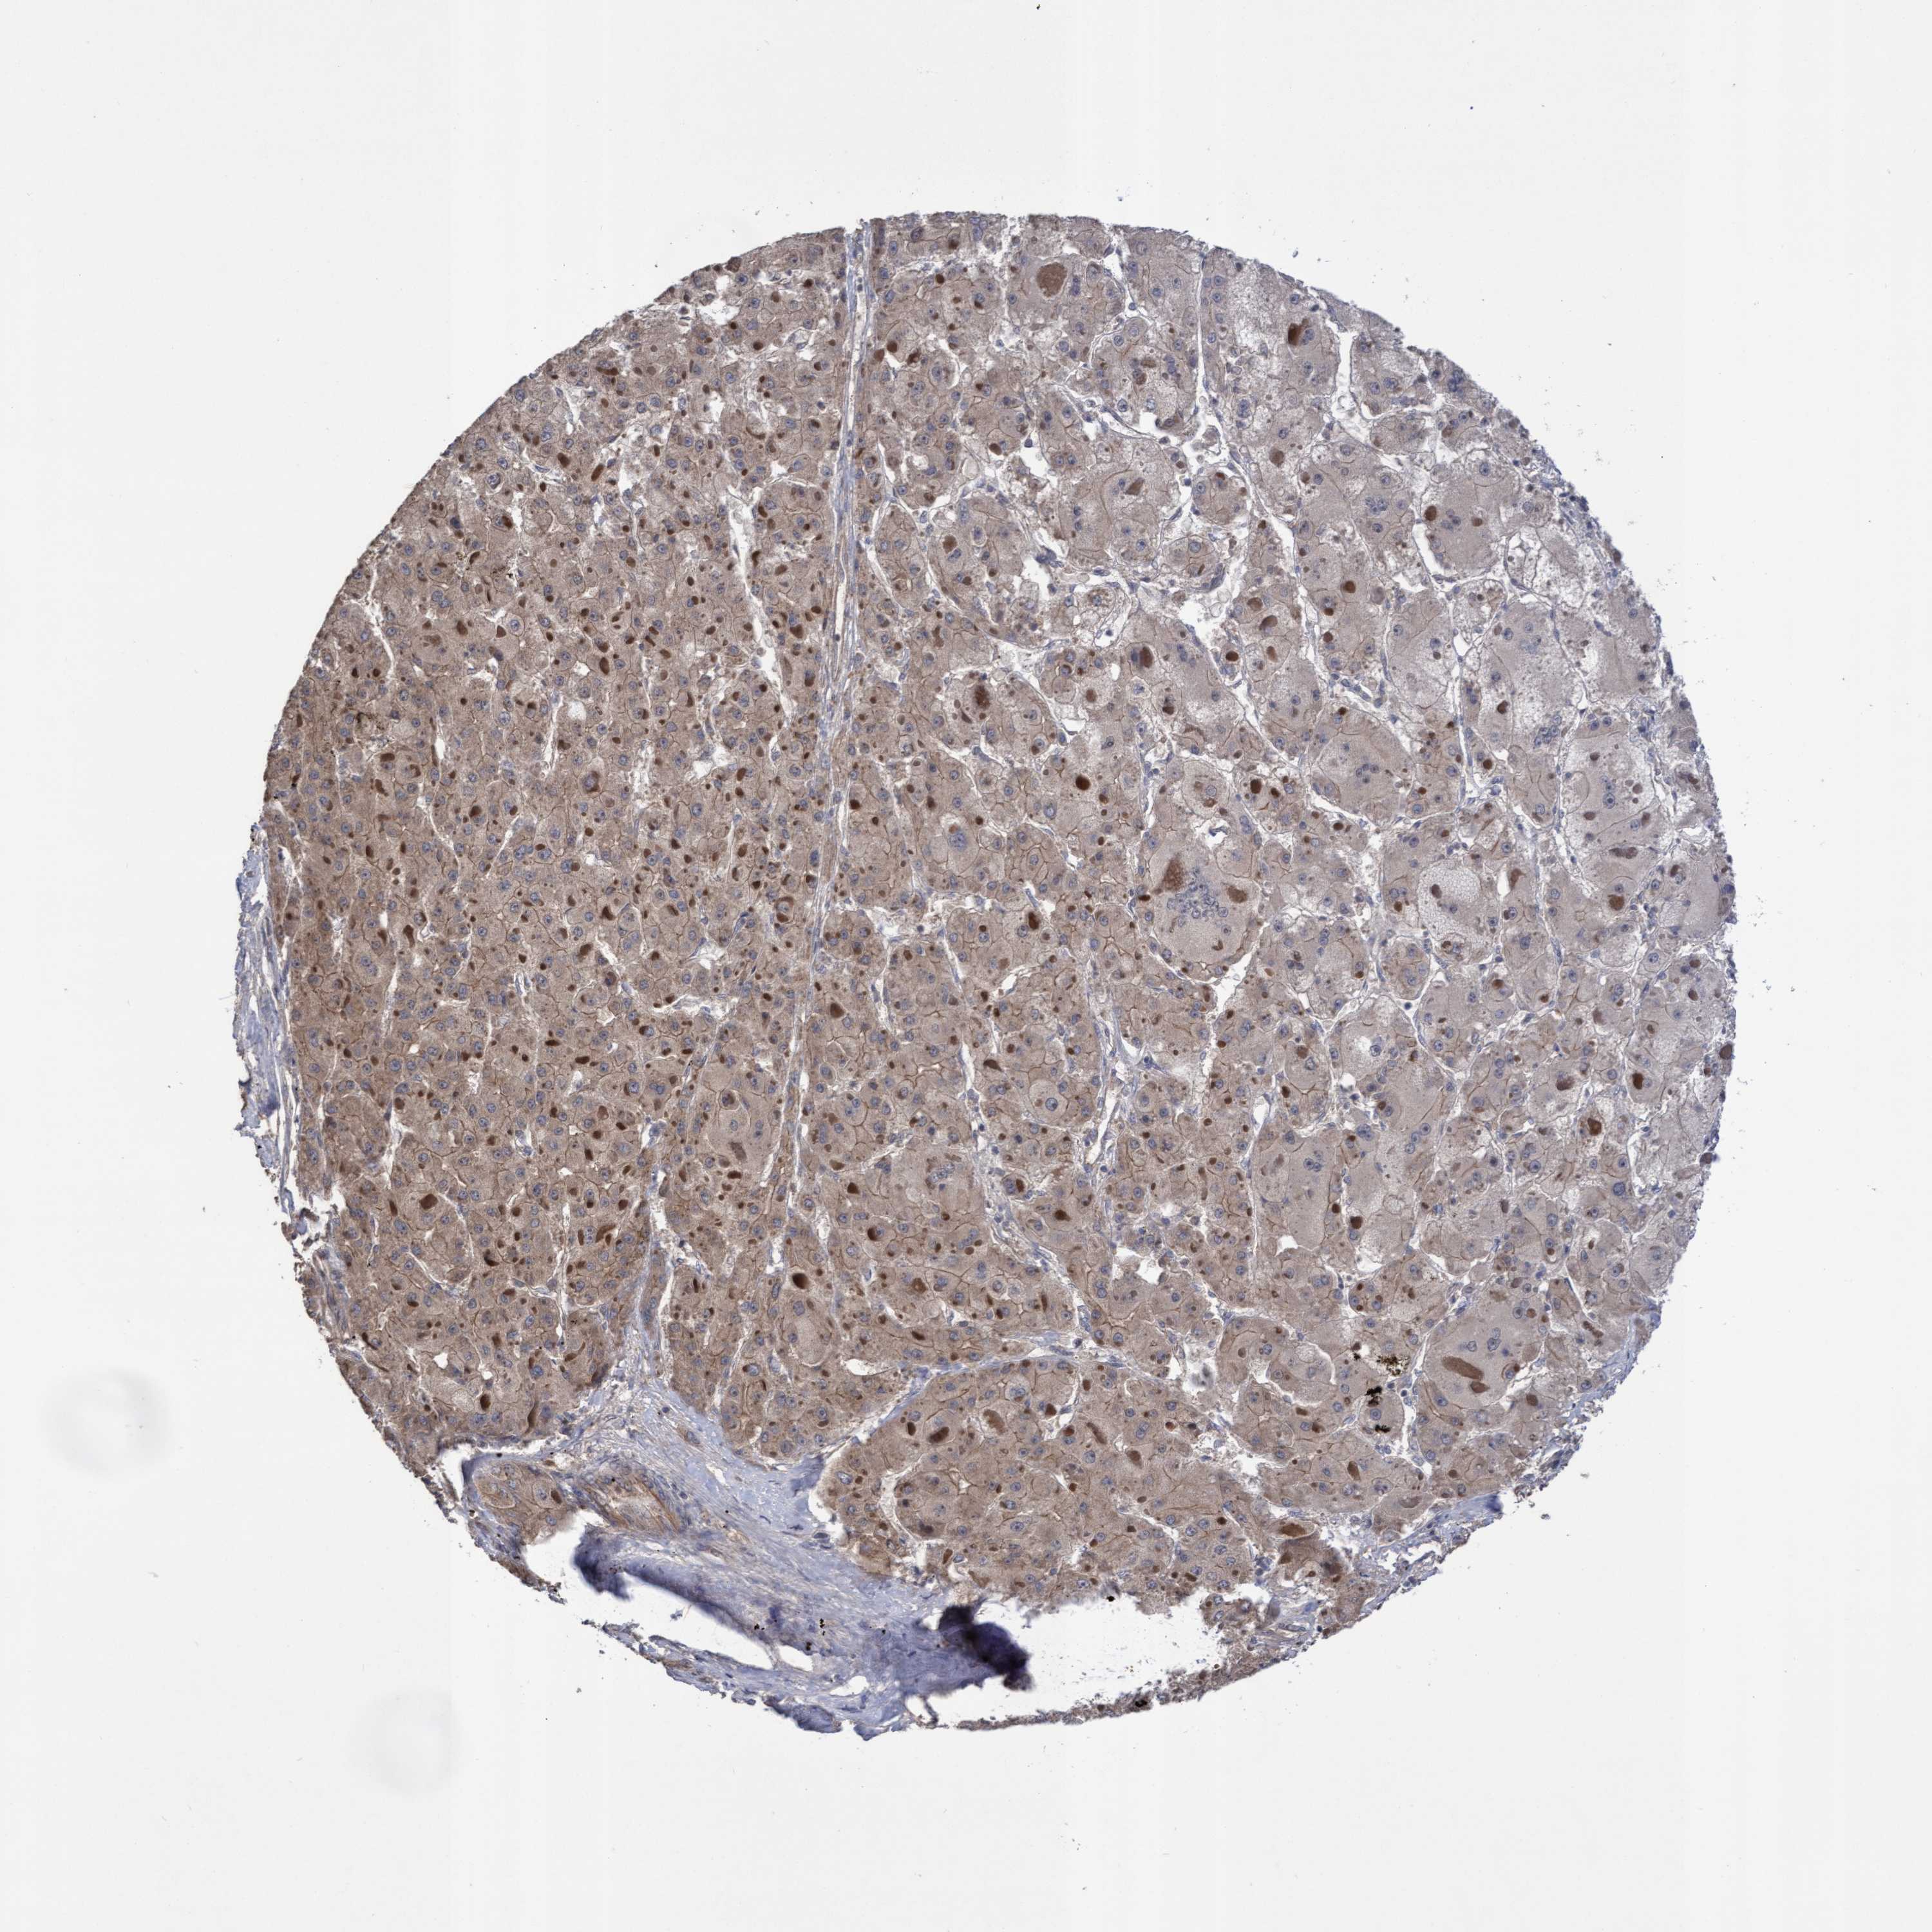

LIVER CANCER - Protein expressioni

A mouse-over function shows sample information and annotation data. Click on an image to view it in a full screen mode. Samples can be filtered based on level of antibody staining by selecting one or several of the following categories: high, medium, low and not detected. The assay and annotation is described here.

Antibody stainingi

Antibody staining in the annotated cell types in the current human tissue is reported as not detected, low, medium, or high, based on conventional immunohistochemistry profiling in selected tissues. This score is based on the combination of the staining intensity and fraction of stained cells.

Each image is clickable and will lead to virtual microscopy that enables deeper exploration of all samples and also displays staining intensity scores, fraction scores and subcellular localization as well as patient and tissue information for each sample.

Antibody HPA019033

Antibody HPA019167

Staining

High

Medium

Low

Not detected

Intensity

Strong

Moderate

Weak

Negative

Quantity

>75%

75%-25%

<25%

None

Location

Nuclear

Cytoplasmic/membranous

Cytoplasmic/membranous,nuclear

Cholangiocarcinoma

Carcinoma, Hepatocellular, NOS